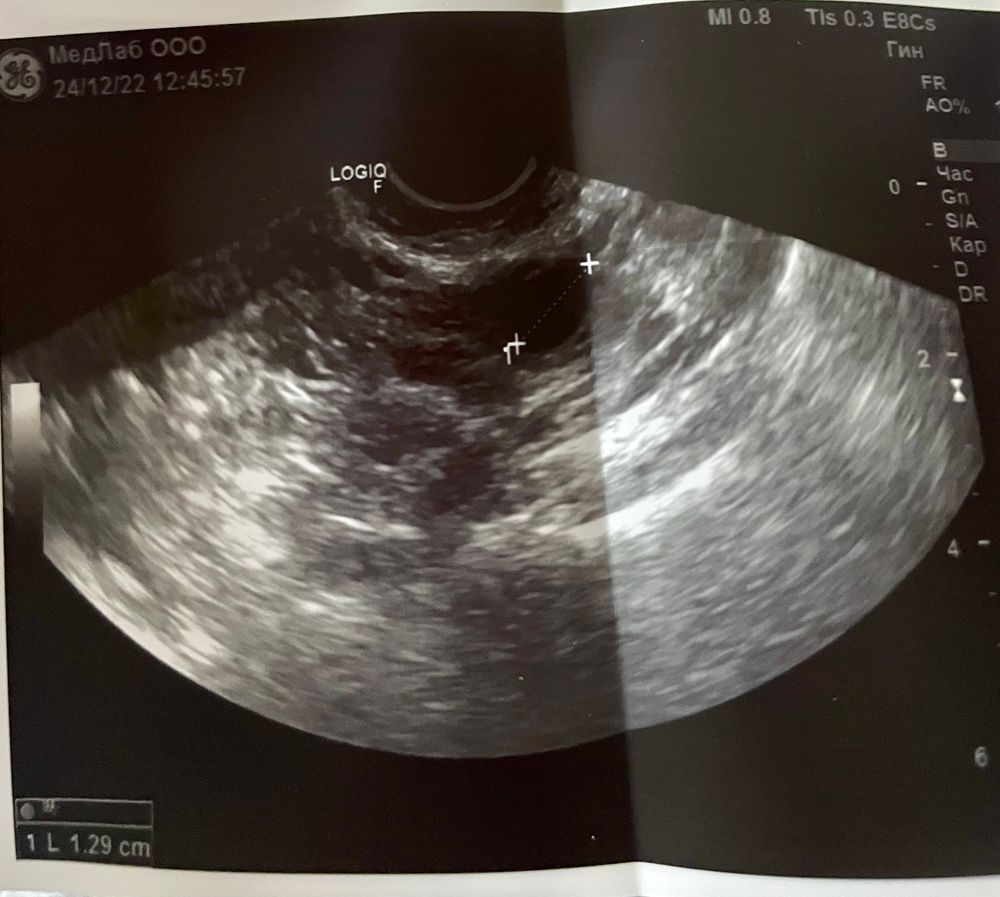

9 дц 🌟 тест уже соответствует дню цикла , вчера было что то не то) узи .. пошла не к своей Ги, конечно пишет одно по фото немного другое ..но похоже овуляция будет в пя 😔.. эндик 6,4 фоллики в ля 13 мм, в пя не пойму по фото но она написала 16 мм